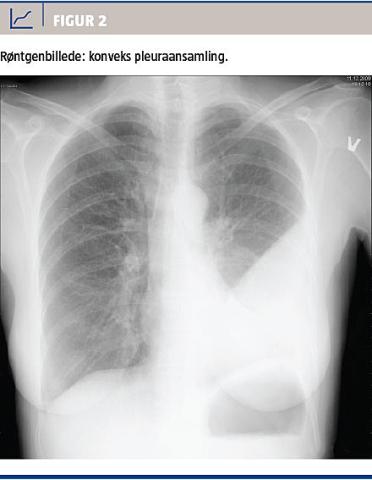

På dag otte blev patientens hustru indlagt med lignende symptomer. Hun kom i antibiotisk behandling med phenoxymethylpenicillin og metronidazol. Man fandt en høj koncentration af C-reaktivt protein på 235 nmol/l og et røntgenverificeret infiltrat på venstre side (Figur 2). Der blev påbegyndt behandling med cefuroxim og metronidazol og anlagt pleuradræn, hvorfra

der kom en purulent, langsomtløbende, træg væske. Patienten kom hurtigt i klinisk bedring og kunne derfor udskrives sammen med sin ægtefælle til peroral antibiotisk behandling. Hun måtte desværre genindlægges efter to uger pga. recidiv af empyem, der dog hurtigt bedredes. Der var positiv polymerasekædereaktion for pneumokokker i pleuravæsken.